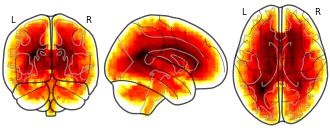

Bootstrapped ratio (BSR) values of canonical correlation analysis (CCA) loadings from age prediction using MRI.

Subject species

homo sapiens

Modality

Structural MRI

Analysis level

group

Cognitive paradigm (task)

None / Other

Map type

Other